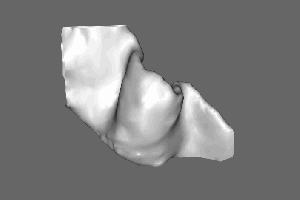

Within the hand knob, you find the double layer response only on the lateral side (M1-4a):